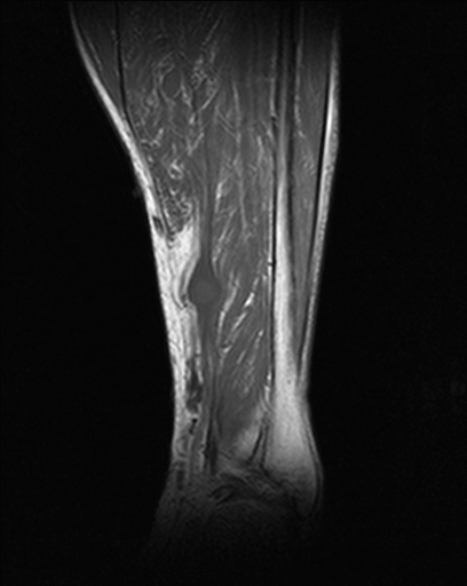

4.2 RM con contraste (prueba de elección)

- T1: señal baja–intermedia respecto a músculo.

- T2/STIR: señal alta, a menudo heterogénea (degeneración quística en schwannomas antiguos).

- Signos orientativos: relación con el nervio (fascículo entrante/saliente), “fascicular sign”, “split-fat sign” (en planos profundos). El “target sign” no es exclusivo.

- Contraste: realce de componente sólido; las áreas quísticas no realzan.